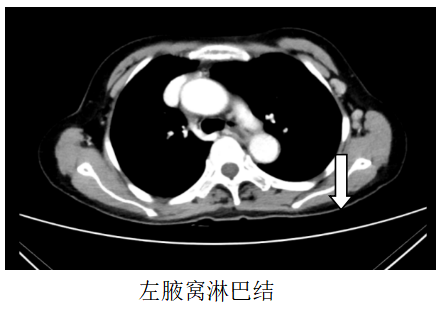

胸部CT:1、左锁骨区、左腋窝多发肿大淋巴结,考虑转移,建议随访,全腹CT:考虑食管胃交界癌累及胃周脂肪并腹腔腹膜后淋巴结多发转移(CT分期约T4aN3)。

诊断:食管胃交界腺癌腹腔、腹膜后、左腋窝、左锁骨区淋巴结转移脑转移(cT4aN3M1,IV期,HER2扩增,MSS,PD-L1-)